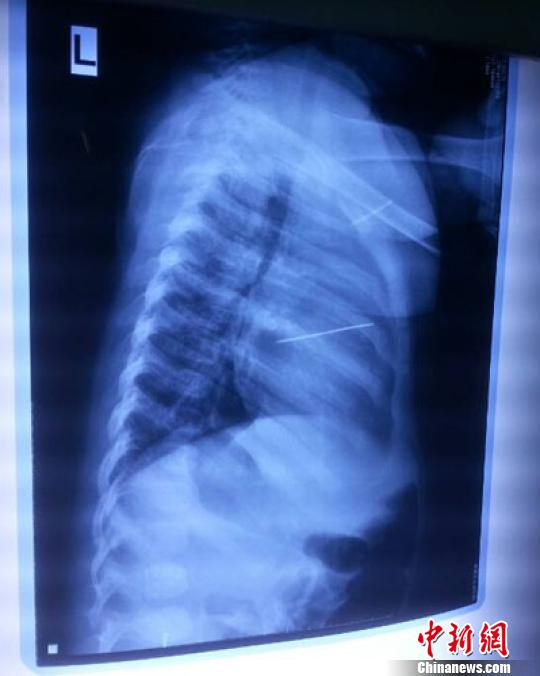

女嬰胸片提示心臟里面扎了一個縫衣針 蔡迅翔 攝

醫(yī)院胸心外科主任翟波介紹說,1月22日,小患者彤彤因為發(fā)燒抽搐來醫(yī)院就診,常規(guī)檢查時發(fā)現(xiàn)孩子心臟里面扎了一個縫衣針。

“第二天上午,我們做了個緊急彩超檢查,發(fā)現(xiàn)針是從患者右心室表面刺入,穿破室間隔,到達左心房,中間還有一部分損害到二尖瓣。于23號下午,我們就做了一個緊急手術,手術中發(fā)現(xiàn),這枚針已經刺入心臟,沒入了右心室的下面,表面已經看不到針了,僅能看到一個小針眼,還在往外滲血,一點一點的滲,心包腔里面大概有100多毫升的出血,心包上一個洞,針在右心室表面刺入以后,穿過室間隔,在二尖瓣的上方,進入了左心房,在針的四周,有很多纖維沉積物,包繞著這枚針?!钡圆ㄕf,他們把針取出來以后,測量了一下,長度大概是五厘米,同時發(fā)現(xiàn)這個針給患者左心房的后壁造成了一定的損傷,左心房的后壁已經損傷了三分之二,還剩下有左心房的外膜,很薄的一層,如果這一層再破的話,這個孩子將會引起大出血,很快就會死亡。